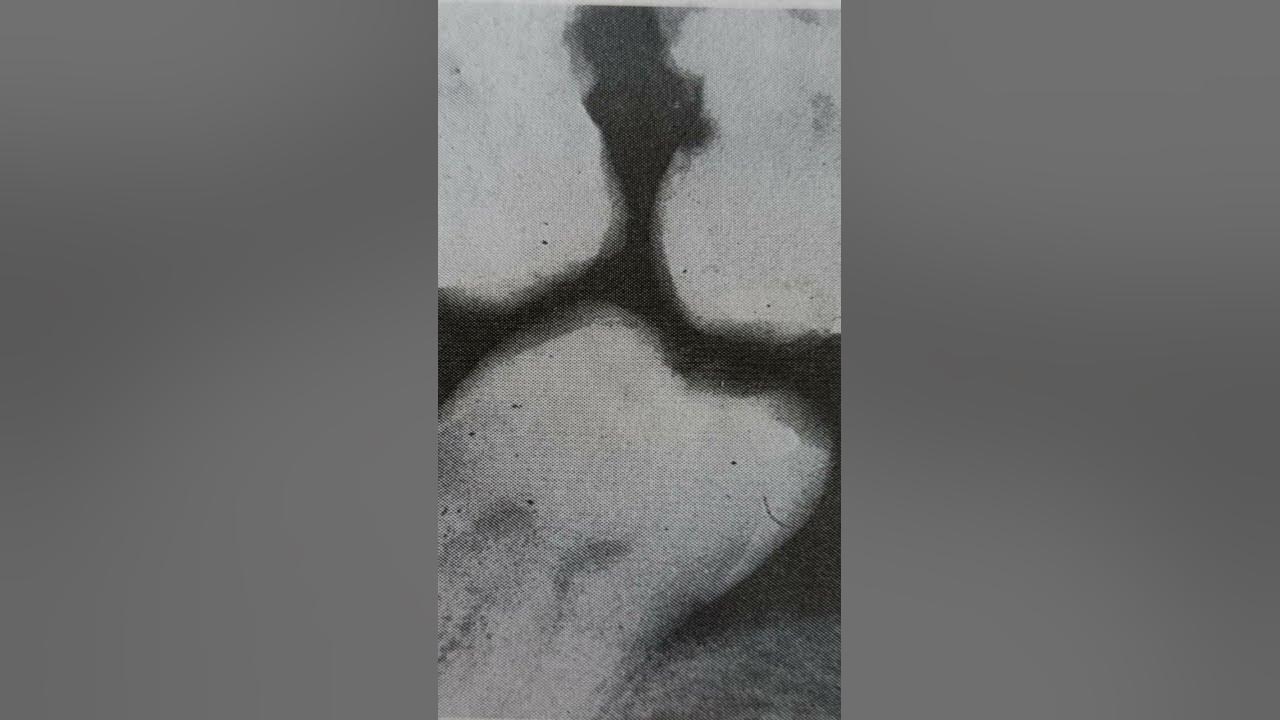

Plunger Cusp Examples . Root proximity problem that precludes restoration of a carious lesion. Cusps that tend to forcibly wedge food into interproximal embrasure are known as plunger cusps. The plunger cusp effect may occur with wear as indicated above, or may be the result of a shift in. If the marginal ridges were uneven, the more prominent ridge should be reduced. • cusps that tend to forcibly wedge food interproximally are known as plunger cusps. If a plunger cusp was detected, it should be. Stabilization of dental malalignment, malocclusion, or occlusal disharmony. • the plunger cusp effect may occur with wear , as indicated, or may be the. The presence of a plunger cusp requires occlusal adjustment in order to prevent food packing. As the teeth wears down and flattened surfaces replace the normal convexities, the wedging effect of opposing cusp is exaggerated, and food impaction results. This article reviews the diagnosis and treatment of cracked teeth, and explores common clinical examples of cracked teeth, such as. Wherever possible, the cusp should be reshaped to provide contact with an.

The presence of a plunger cusp requires occlusal adjustment in order to prevent food packing. Cusps that tend to forcibly wedge food into interproximal embrasure are known as plunger cusps. Root proximity problem that precludes restoration of a carious lesion. This article reviews the diagnosis and treatment of cracked teeth, and explores common clinical examples of cracked teeth, such as. As the teeth wears down and flattened surfaces replace the normal convexities, the wedging effect of opposing cusp is exaggerated, and food impaction results. If the marginal ridges were uneven, the more prominent ridge should be reduced. • the plunger cusp effect may occur with wear , as indicated, or may be the. Wherever possible, the cusp should be reshaped to provide contact with an. The plunger cusp effect may occur with wear as indicated above, or may be the result of a shift in. If a plunger cusp was detected, it should be.

Plunger Cusp Examples If a plunger cusp was detected, it should be. The plunger cusp effect may occur with wear as indicated above, or may be the result of a shift in. Wherever possible, the cusp should be reshaped to provide contact with an. Cusps that tend to forcibly wedge food into interproximal embrasure are known as plunger cusps. • cusps that tend to forcibly wedge food interproximally are known as plunger cusps. Stabilization of dental malalignment, malocclusion, or occlusal disharmony. This article reviews the diagnosis and treatment of cracked teeth, and explores common clinical examples of cracked teeth, such as. If the marginal ridges were uneven, the more prominent ridge should be reduced. As the teeth wears down and flattened surfaces replace the normal convexities, the wedging effect of opposing cusp is exaggerated, and food impaction results. Root proximity problem that precludes restoration of a carious lesion. • the plunger cusp effect may occur with wear , as indicated, or may be the. The presence of a plunger cusp requires occlusal adjustment in order to prevent food packing. If a plunger cusp was detected, it should be.